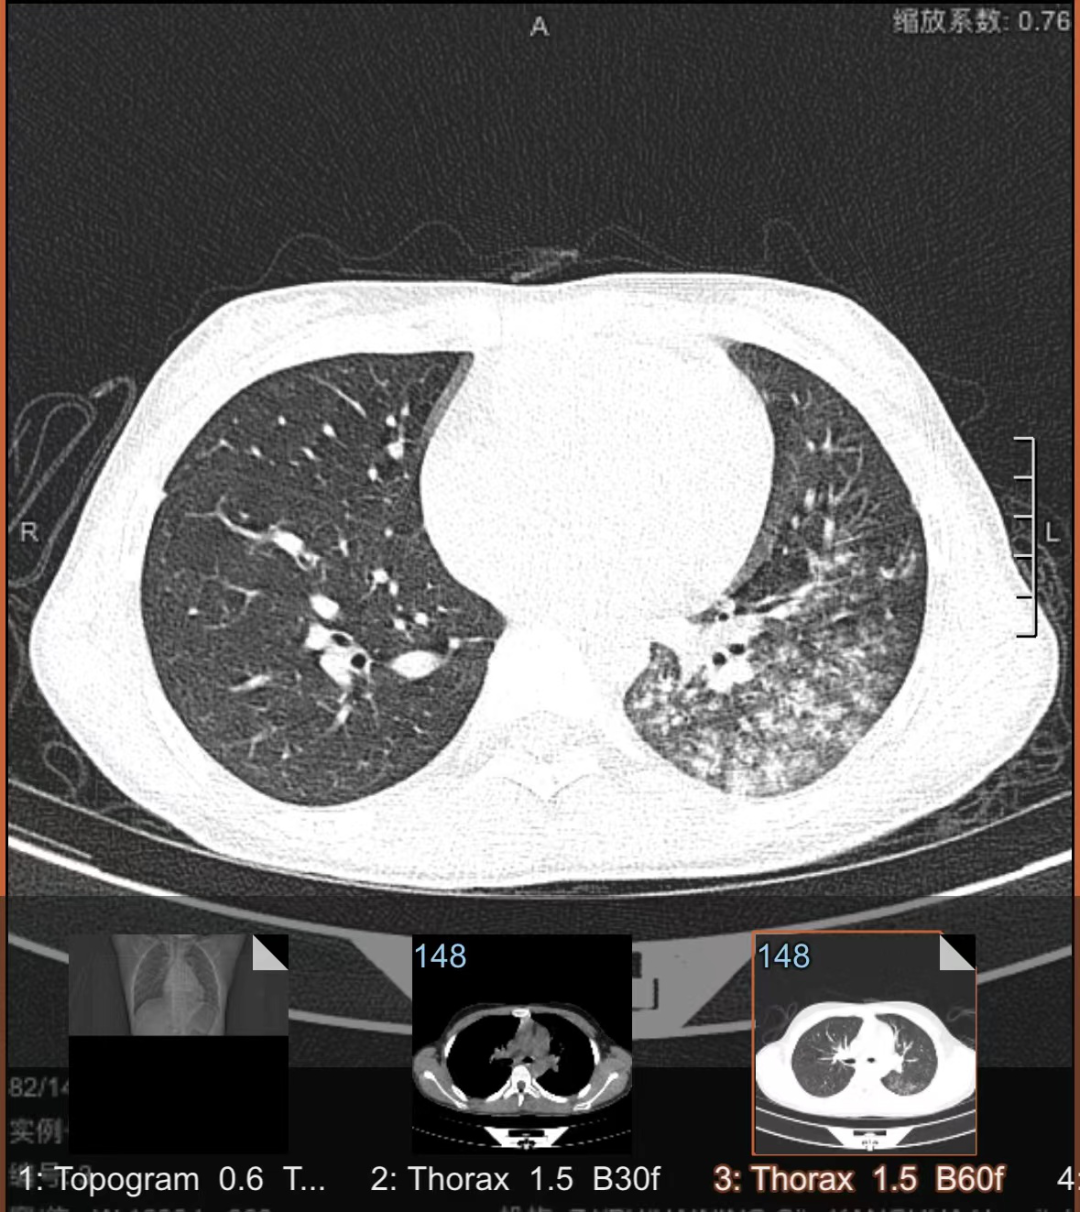

一拍片发现肺部出现了炎症

还融合成了片状

支原体呼吸道感染临床表现呈多样性,可从无无症状到鼻咽炎、鼻窦炎、中耳炎、扁桃体炎、气管支气管炎和肺炎等,肺炎支原体肺炎的主要临床表现是发热、咳嗽、肺部体征与临床症状及影像所见不一致。

只有少部分感染者会发展为肺炎。肺炎支原体肺炎(MPP)以发热、咳嗽为主要临床表现,可伴有头痛、流涕、咽痛、耳痛等。发热以中高热为主,持续高热者预示病情重。咳嗽较为剧烈,可类似百日咳样咳嗽,婴幼儿以喘息为主要表现多见。肺部早期体征可不明显,随着病情进展可出现呼吸音降低和干、湿性啰音。